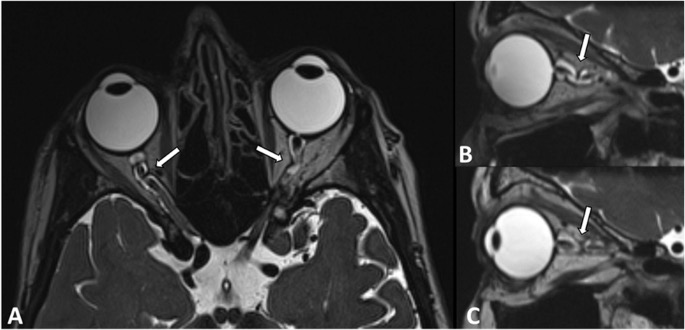

There appears to be a significantly higher incidence of optic nerve kinking in individuals with normal tension glaucoma (NTG) compared to healthy controls. This finding was discovered after retro-bulbar/orbital optic nerve imaging utilizing CT cisternography and MRI in 57 NTG patients vs 57 age and gender-matched controls.

The results were extraordinary with 86% of NTG patients showing optic nerve kinking in the axial plane, compared to only 18% of controls. In the sagittal plane, 49% of NTG patients exhibited kinking versus just 2% of controls. These findings suggest a likely link between altered optic nerve anatomy and NTG pathophysiology. Kinking may influence cerebrospinal fluid dynamics within the subarachnoid space of the optic nerve, contributing to the development and/or progression of glaucomatous optic neuropathy.

While further studies are needed to fully understand and confirm this relationship, these results highlight potential anatomic retro-bulbar pathophysiology in NTG patients. We now may want to consider ordering orbital MRI's, particularly for NTG patients with progressive optic neuropathy and/or visual field loss.